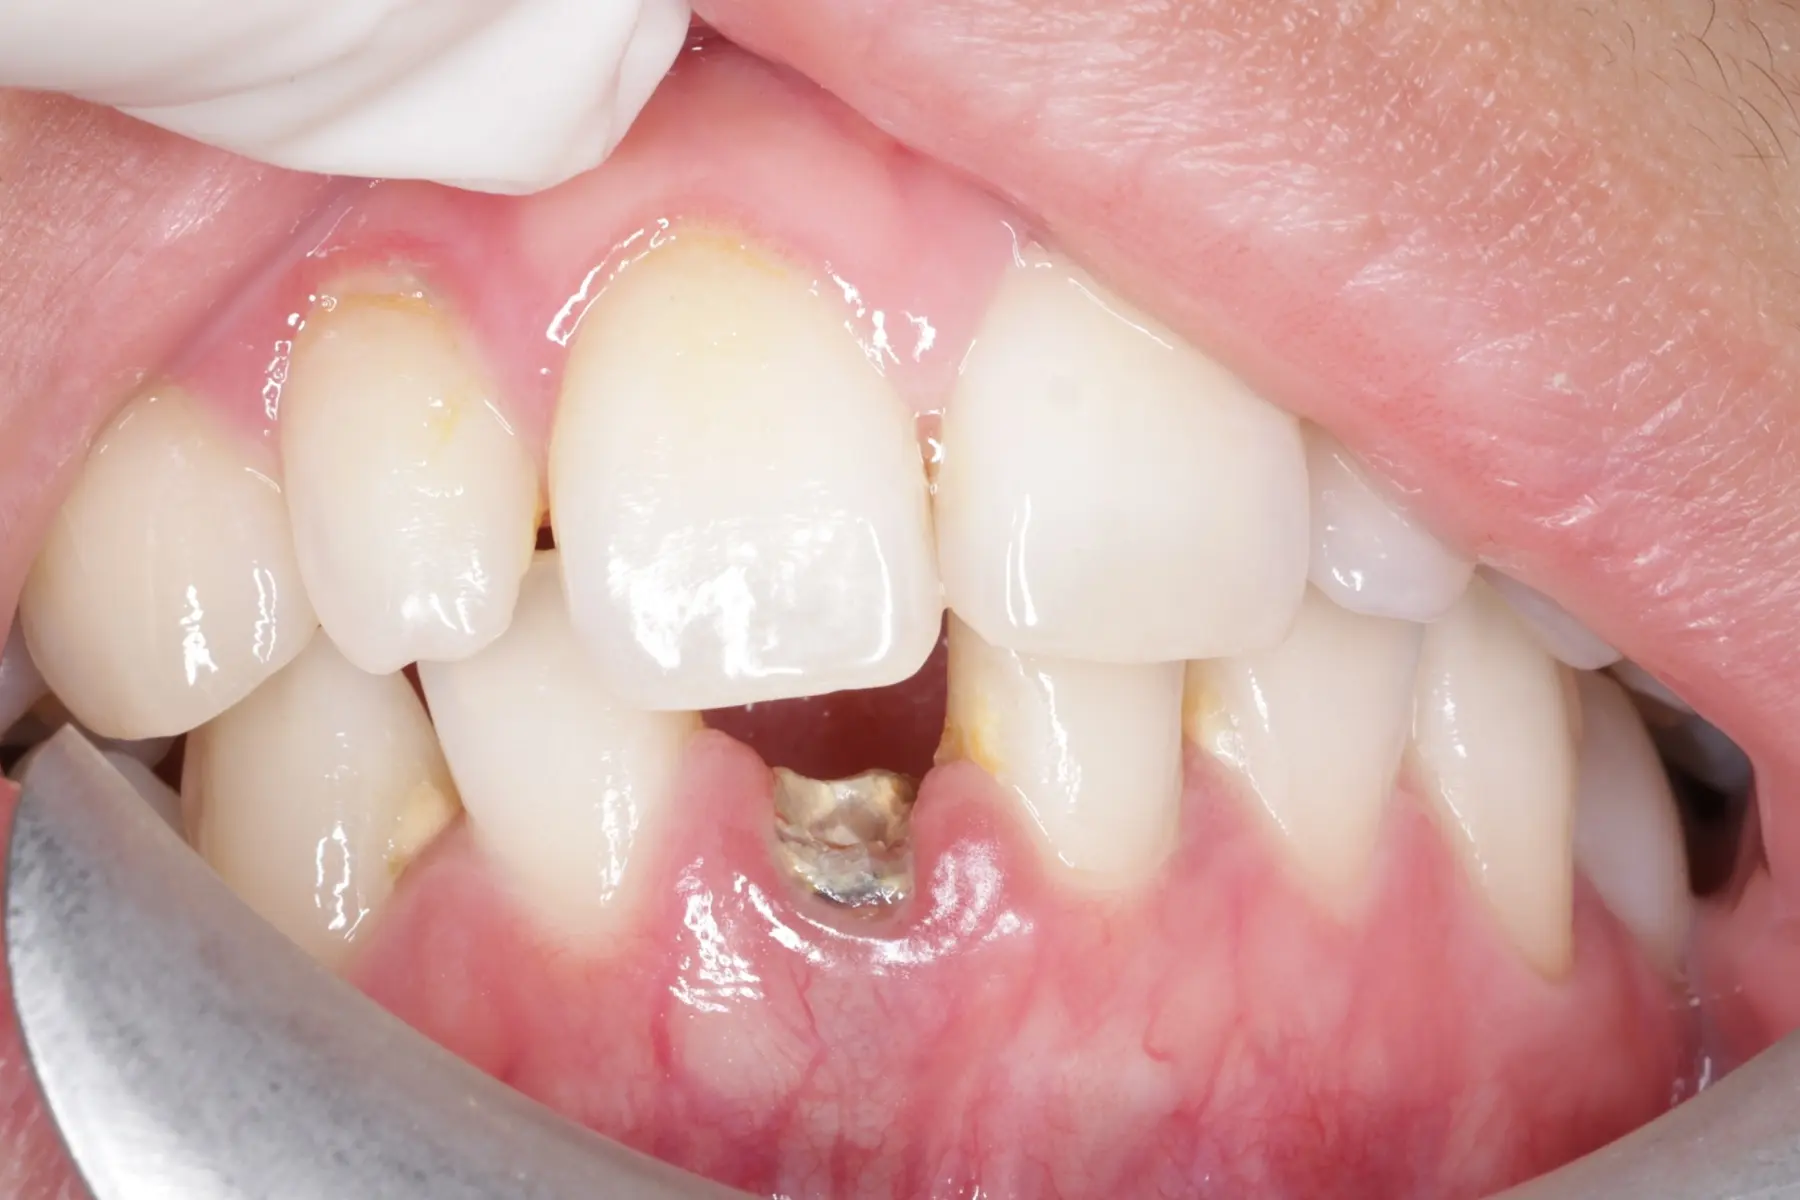

牙橋

主治醫師

• 楊明憲

治療時間

約1年4個月

主訴

吃東西左邊後牙會痛